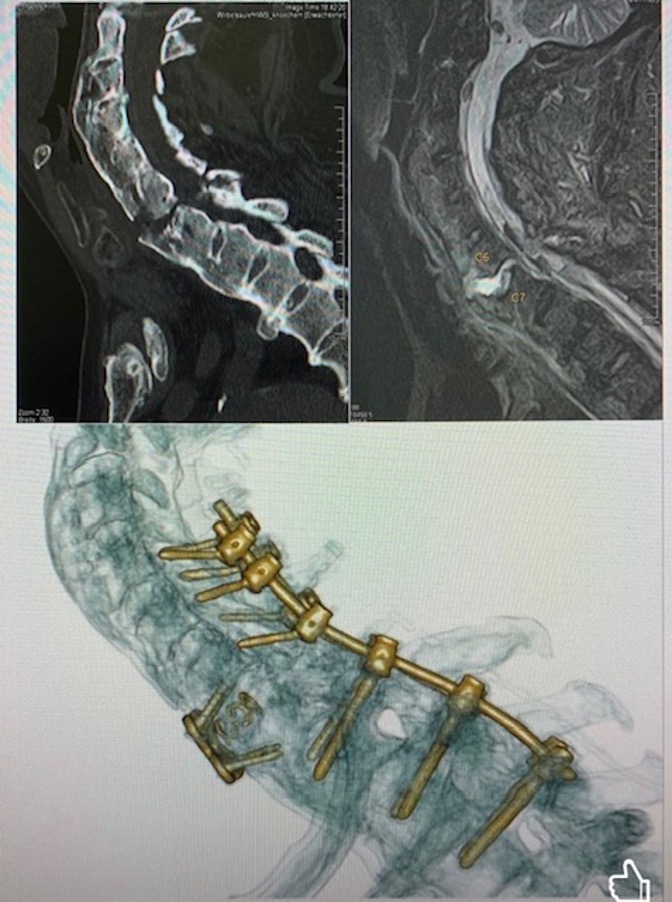

Case3 Patient from Germany. cervical Fracture by Ankylosing Spondylitis patient who fell at home at home and developed unstable fracture

Here we addressed the fracture promptly and managed to stabilise it.